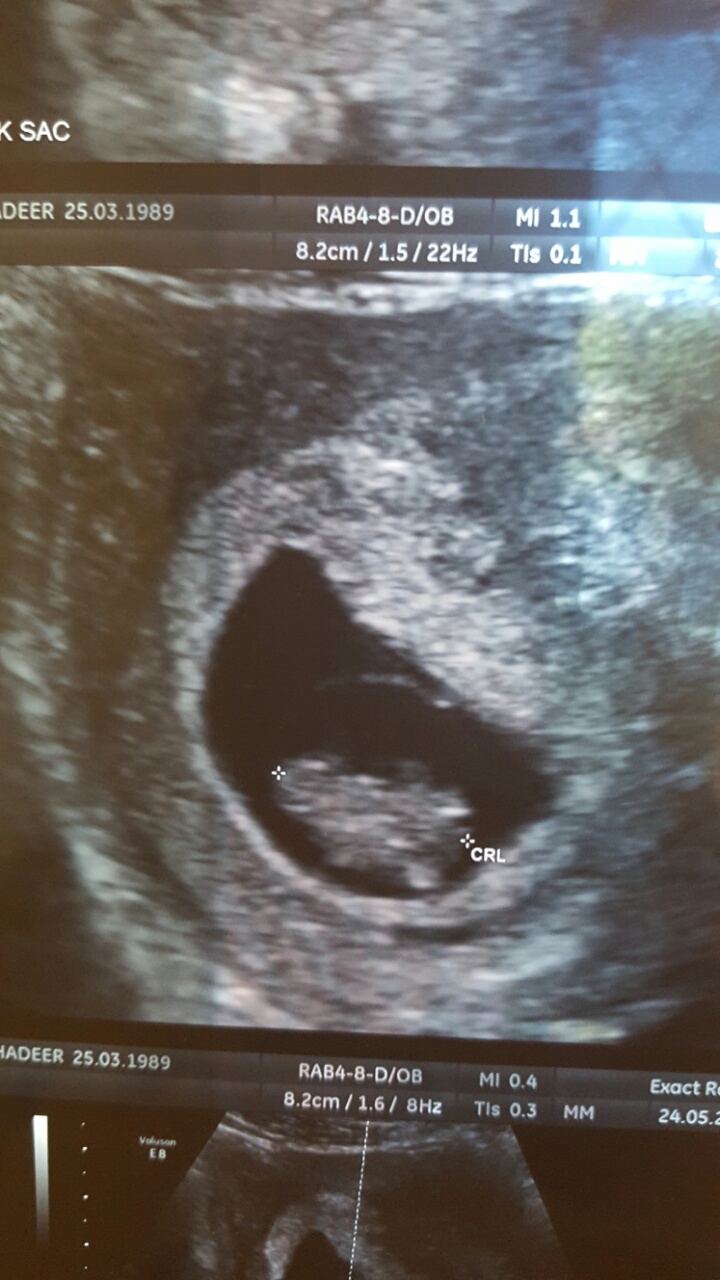

وهذا شكل الولد

اما البنت بالاسبوع 7 و5 ايام يعني اكبر بس ماواضحه